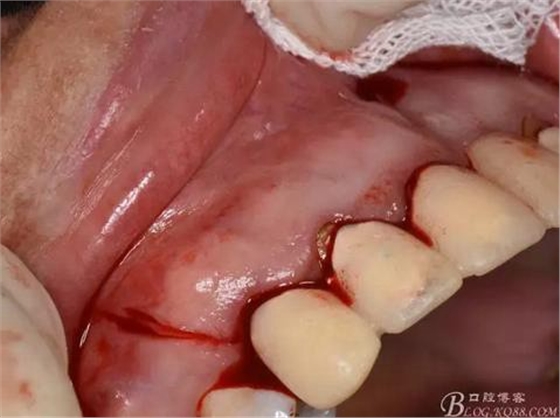

圖7.分別在13的遠(yuǎn)中和11的近中做垂直切口加齦溝內(nèi)水平切口,形成梯形瓣